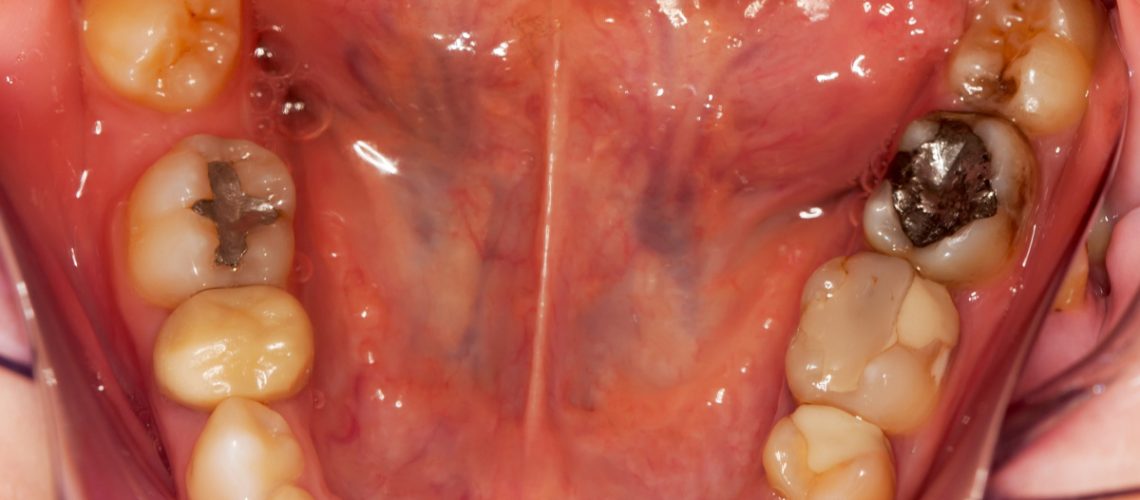

There is a reason amalgam fillings are banned in many European countries, and why a holistic dentist would avoid any use of amalgam in his or her dental practice.

There is a reason amalgam fillings are banned in many European countries, and why a holistic dentist would avoid any use of amalgam in his or her dental practice.

Amalgam fillings, also deceptively called “silver fillings” (deceptive because they contain very little silver), are made up of over 50% mercury—a toxic heavy metal that can cause a number of adverse health effects. Mercury exposure can poison the body and cause serious health problems, especially neurological and mental/emotional problems.

One reason why amalgam is so dangerous is because over time, the high heat of chewing and the mechanical action of the tooth rubbing against adjacent teeth causes the release of mercury vapor (the same way your thermometer gives off mercury if you break it). If you have mercury fillings, the vaporized mercury is inhaled by you as well as everyone around you on a daily basis.

There are many Mesa dentists that specialize in safe removal of amalgam fillings without damaging your teeth or jawbone. Then they replace them with composite fillings which are made out of resin, which mimics the look of natural tooth enamel. This provides a more biocompatible and aesthetically appealing alternative to the dental amalgam filling.

- Give off an unnatural appearance that many people dislike (“metal mouth”).